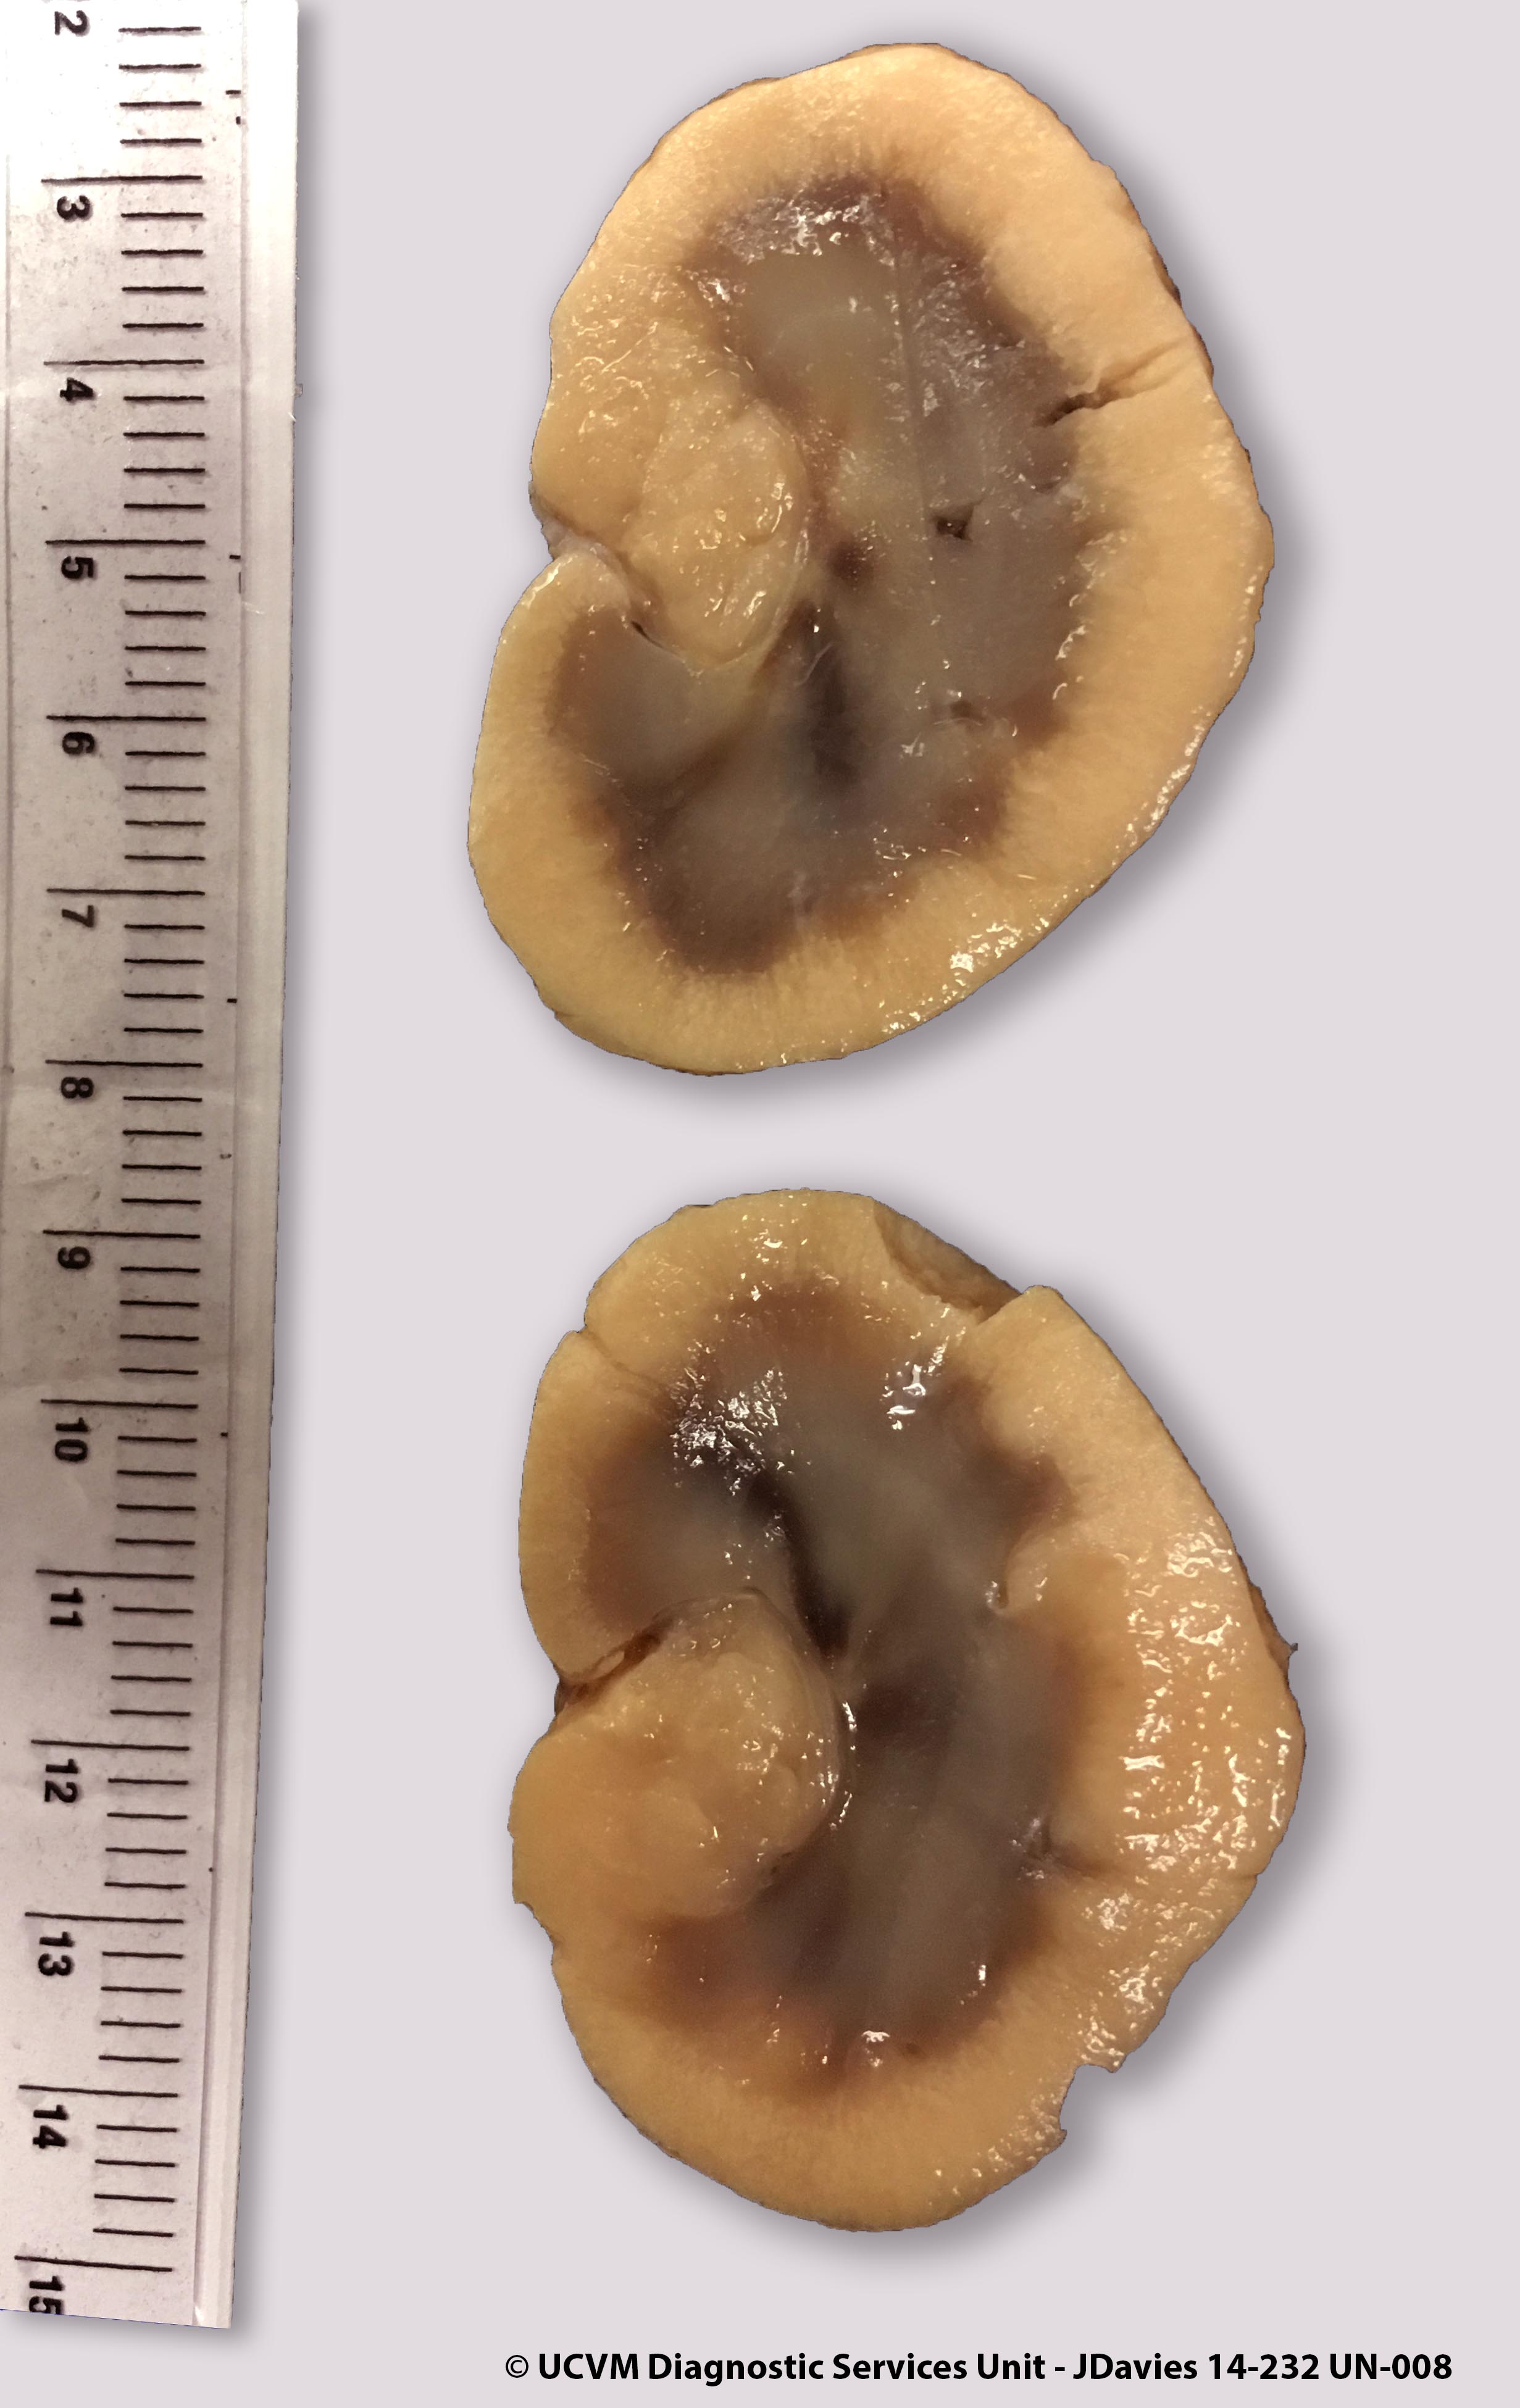

Species: Cat

Specimen: Kidneys

Shown: Lymphoma, lymphosarcoma, LSA